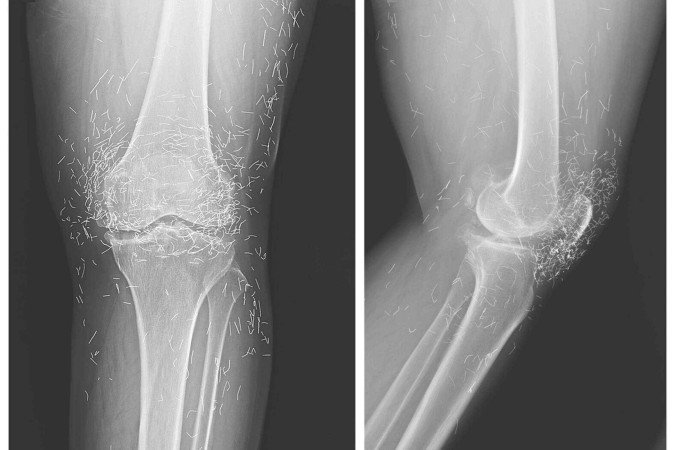

Uma radiografia de rotina revelou algo inesperado no joelho de uma mulher de 65 anos: dezenas de pequenos pontos brilhantes espalhados ao redor da articulação. A imagem denunciava a presença de fios de ouro no joelho da paciente como parte de um tratamento alternativo para dor. O caso, descrito no New England Journal of Medicine, acende um alerta sobre os riscos de terapias sem comprovação científica.

Esses fios, contudo, não são absorvidos pelo organismo. Permanecem no local onde foram inseridos e podem se acumular em regiões já comprometidas, como articulações afetadas pela osteoartrite. No caso relatado, além de não aliviar a dor, os implantes passaram a interferir diretamente na investigação clínica.

A presença de metal no corpo impõe desafios importantes aos exames de imagem. Embora alguns tipos de ouro e aço inoxidável sejam considerados compatíveis com a ressonância magnética sob condições específicas, o uso exige cautela rigorosa. Fatores como composição, tamanho e localização do material determinam se o exame pode ou não ser realizado. Fios de ouro puro, por exemplo, são classificados como “condicionais”, o que significa que a ressonância só pode ocorrer dentro de parâmetros estritos de segurança.

Mesmo quando o exame é permitido, os metais podem gerar distorções nas imagens — os chamados artefatos — que dificultam a visualização de estruturas essenciais, como cartilagem, sinóvia (revestimento da articulação) e vasos sanguíneos. No caso da paciente, os fios comprometeram a nitidez das imagens, atrasando a avaliação adequada da progressão da doença.